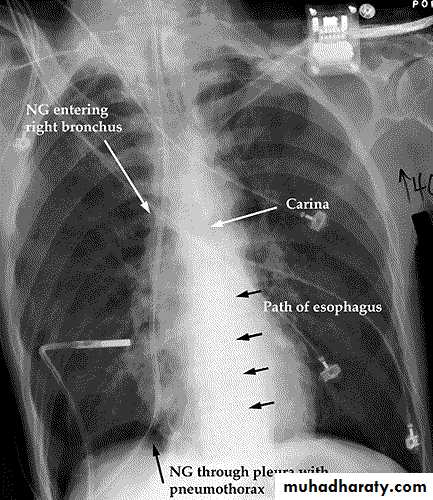

Iatrogenic trauma

NG tubes:

-coiling

-endobronchial placement

-pneumothorax

Chest tubes:

- subcutaneous

- intraparenchymal

- intrafissural

Central lines:

- neck

- coronary sinus

- pneumothorax